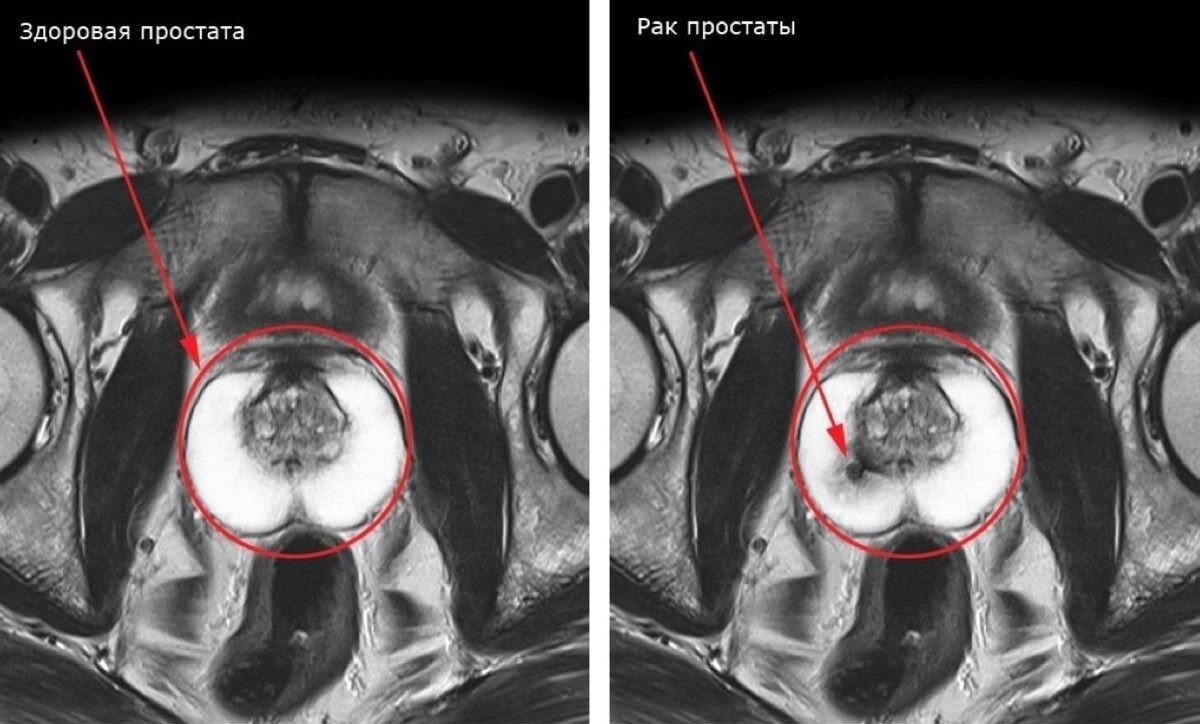

Рак простаты, к которому всегда приводит простатит – вопрос лишь времени

Рак простаты, вышедший за пределы предстательной железы и поразивший близ расположенные ткани.